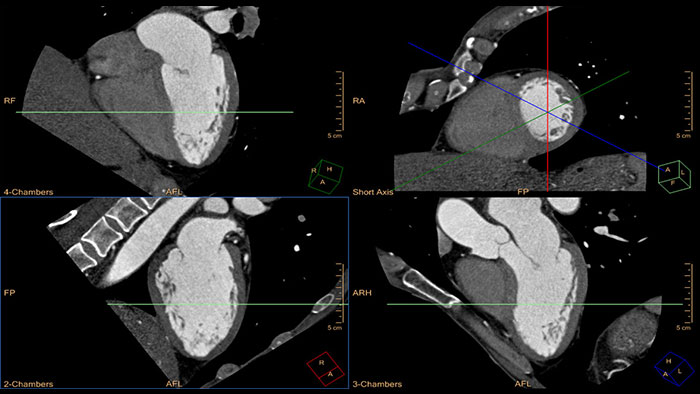

Quick cardiac visualization

Provides a comprehensive set of tools that allows quick visualization of one or multiple cardiac phases.